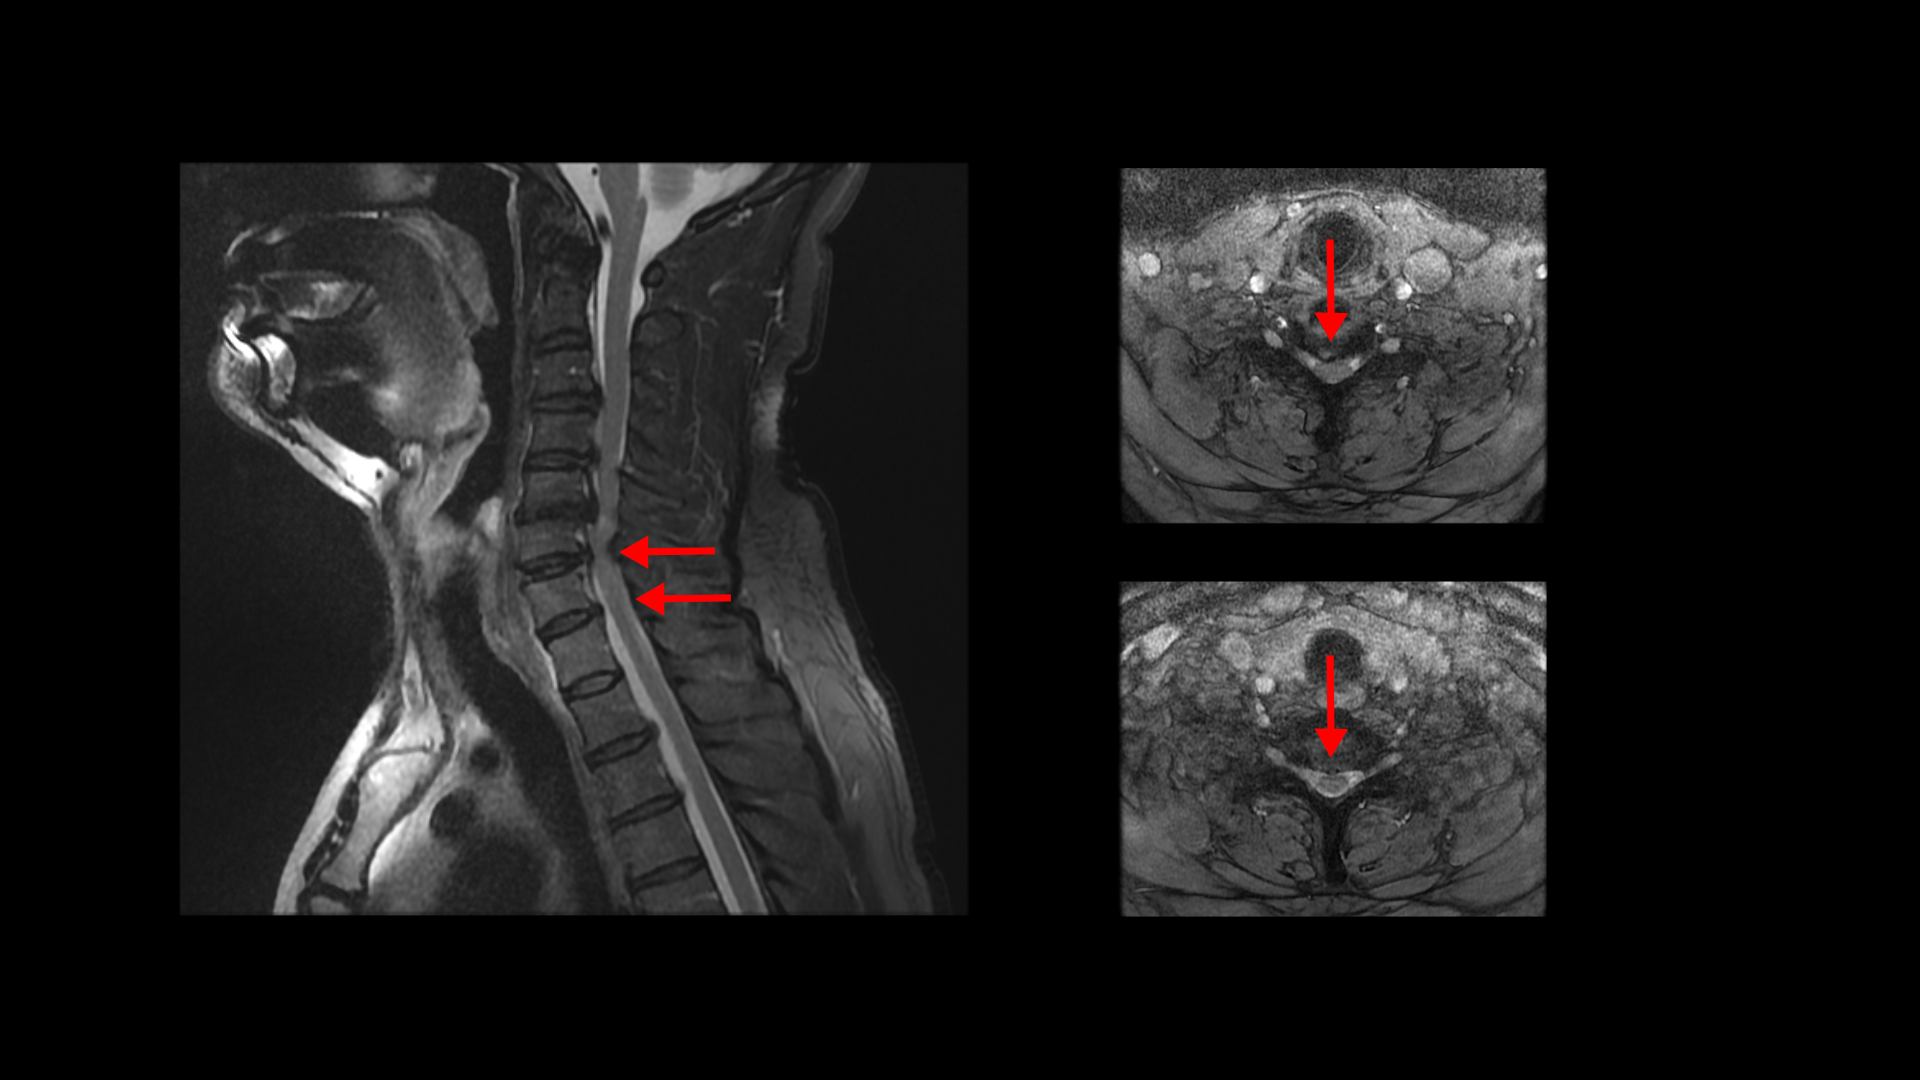

경추척수증이 발생할 경우 이 환자분처럼 양쪽 팔과 손에 증상이 나타납니다. 뿐만 아니라 양쪽 다리에 힘빠짐 증상과 함께 균형을 잘 잡지 못하며 발을 헛딛는 증상도 나타납니다. 만일 적절한 치료를 받지 못한 상태로 병이 계속 진행되면 하반신 마비나 사지마비 등의 심각한 후유증이 남을 수 있습니다.

현대 의학에서는 척수증은 수술만이 유일한 해결 방법이며 병이 더 진행하기 전에 수술로 척수신경에 대한 압박을 줄여줘야 병의 진행을 막는데 도움이 된다고 말합니다. 그런데 저희가 경추에 대한 재활치료를 하다 보면 의외로 척수증 환자 중에서도 수술 없이도 척수증 증상이 호전되는 경우가 있습니다.

특히 목디스크로 인한 척수증일 때 호전가능성이 제일 높습니다. 왜냐하면 저희 치료도 목 주변의 단축되고 뭉쳐있는 근육에 대한 재활치료를 통해 척수 신경에 대한 압박을 풀어주기 때문입니다. 이런 내용을 현대의학에서는 본 적도 들은 적도 없기 때문에 호전결과를 보여줘도 잘 믿지를 못합니다.

모커리 경추척수증 ABCDE 한·양방협진 재활치료법은 수술 없이 경추척수증을 치료하는 모커리 고유의 비수술 치료방법입니다. 경추척수증은 척수에 영향을 미치고 있는 목 주변의 단축되고 뭉쳐 있는 여러 근육들을 풀어주고, 그 근육들의 기능을 살려주어 잘 버틸 수 있게 해주면, 척수 신경압박이 줄어들면서 수술 없이도 증상이 호전될 수 있습니다.